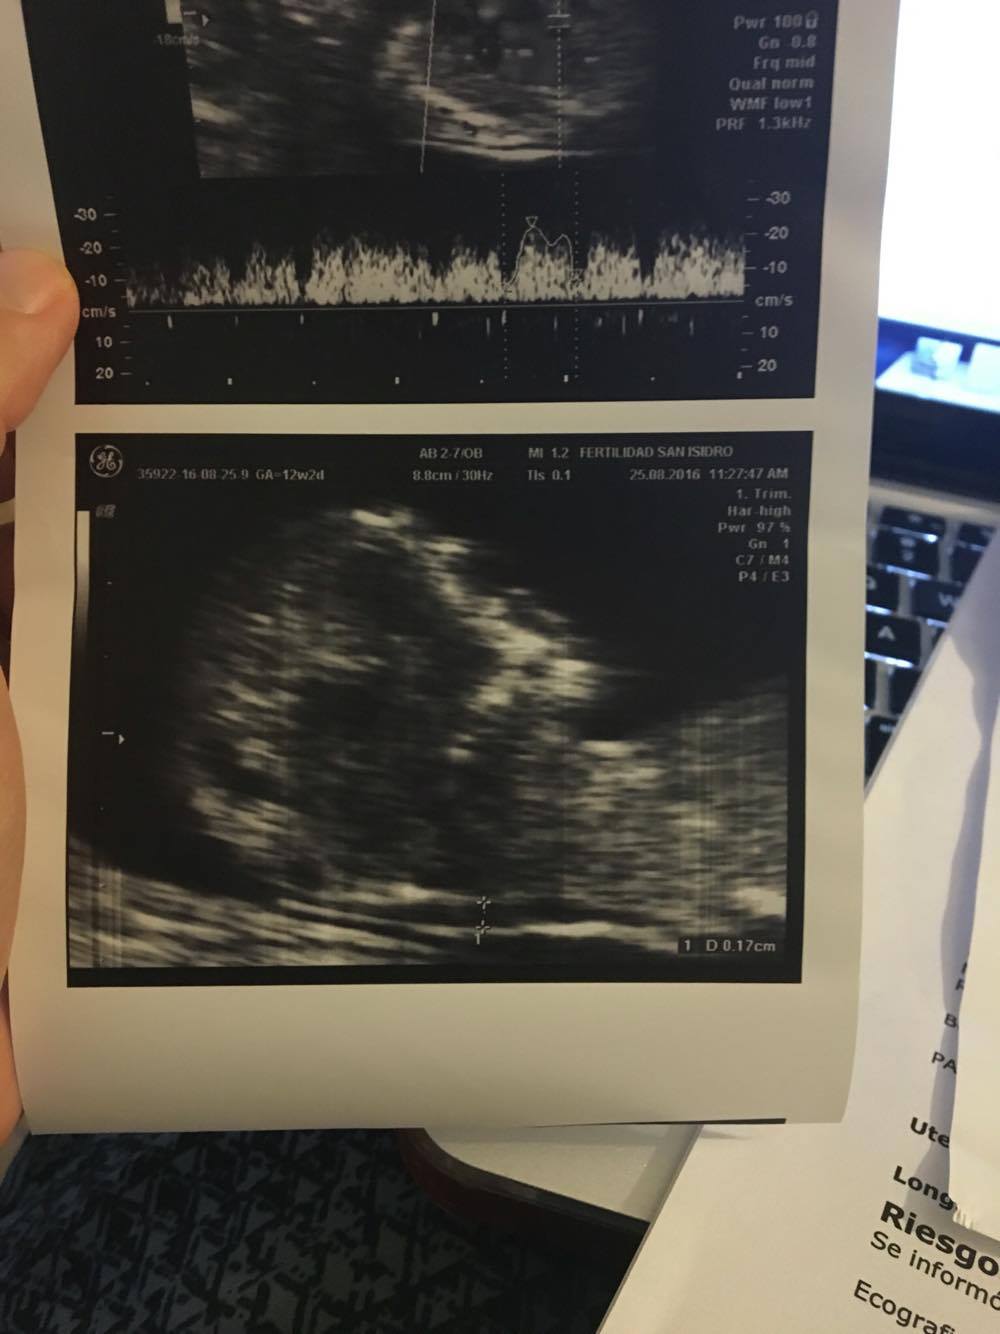

mmm, this two help you?Attachment 32998

Boy [emoji170]

boy

Not sure, 60/40 boy/girl from me.

Boy.

Thinking boy